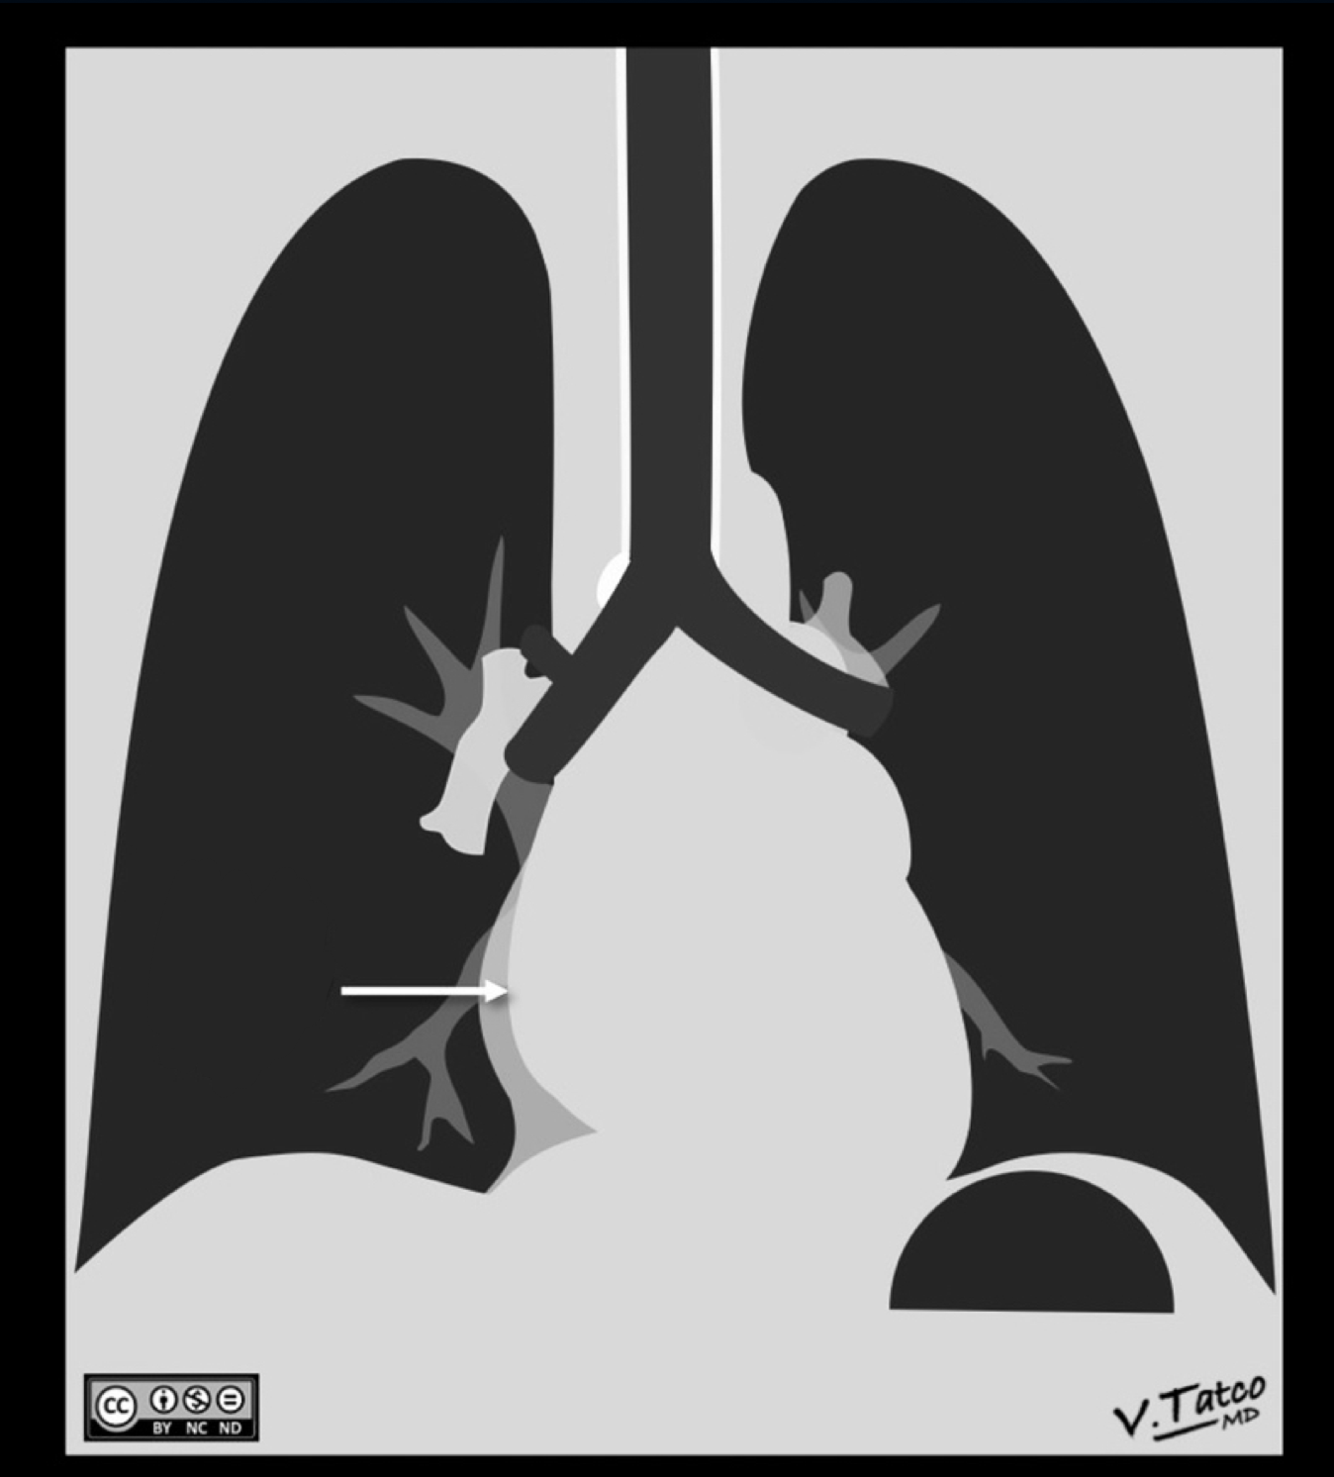

Label the heart chambers